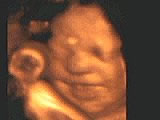

Улыбка в утробе матери

Исследования с помощью ультразвука показали, что дети начинают улыбаться еще в материнской утробе. Британская телекомпания ITV сообщает, что увеличенные изображения наглядно показывают улыбку еще нерожденного младенца.

Ранее предполагали, что дети начинают улыбаться только после появления на свет и научаются улыбке у матери. Однако лондонский профессор Стюарт Кемпбелл (Stuart Campbell) применил новую технологию сканирования и получил изображения младенцев в утробе матери, которые улыбаются, плачут, зевают и мигают.

Профессор Кемпбелл отмечает: "Замечательно то, что дети обычно не улыбаются примерно в течение шести недель после рождения. Однако до рождения они улыбаются весьма часто. Это может означать, что младенец чувствуется себя спокойно и не ощущает никаких проблем в утробе".